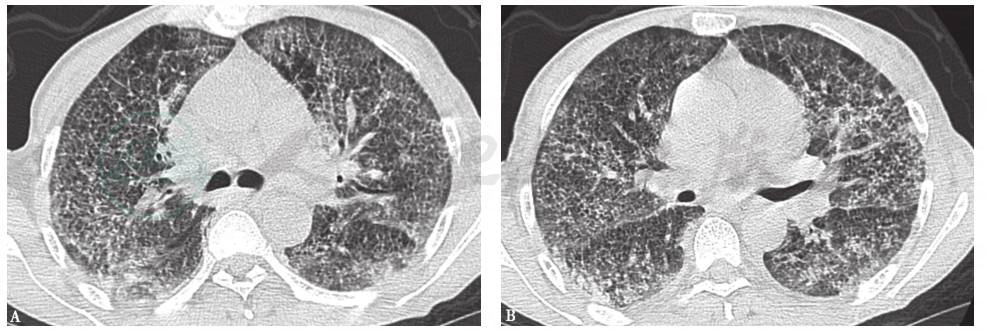

17个月前胸部CT见双肺弥漫性小结节(图1)。

图1 17个月前胸部CT表现